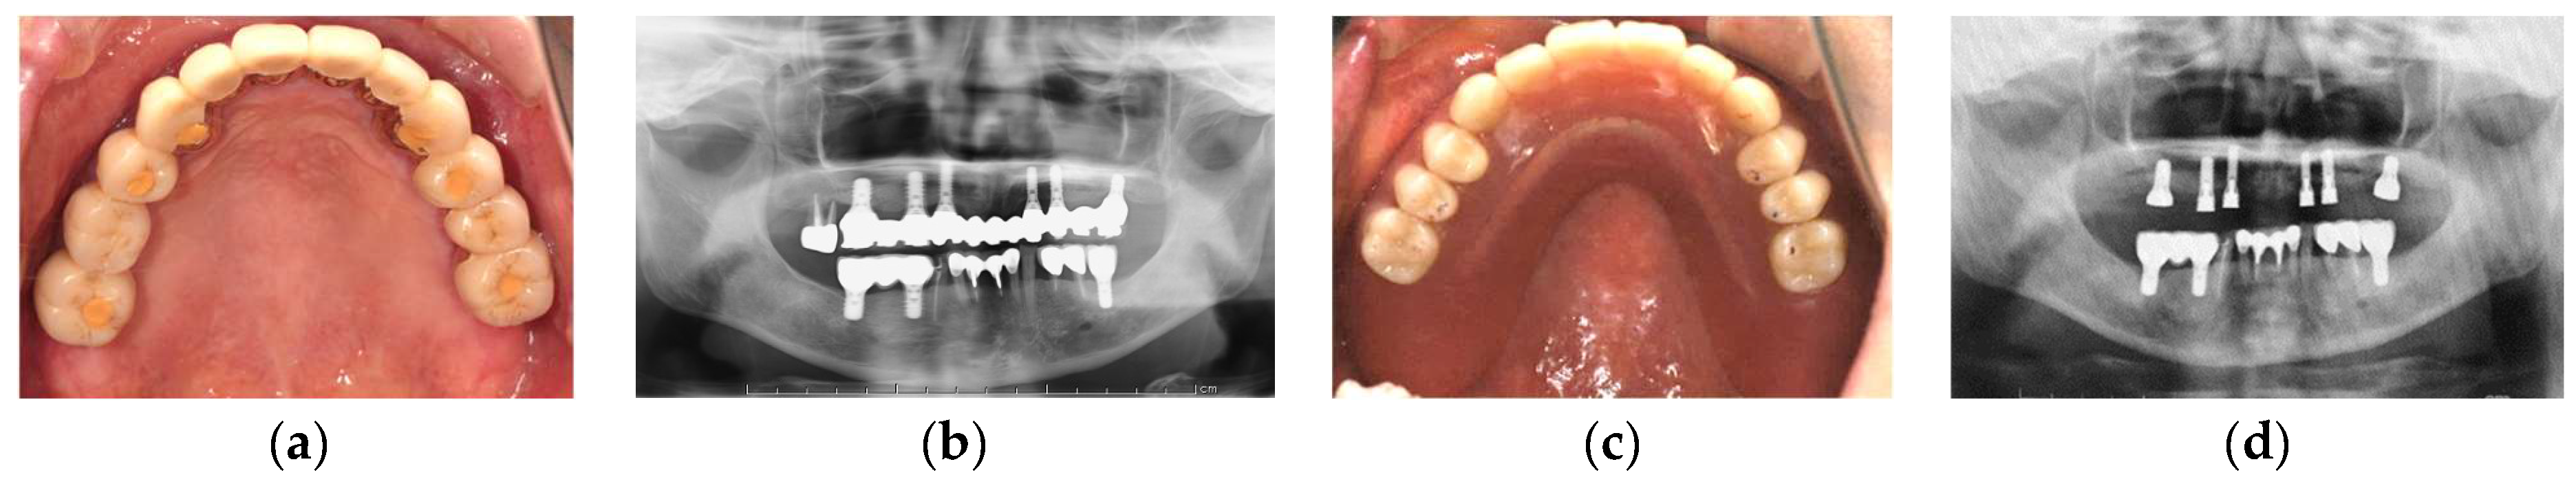

3.3. Conversion of the Suprastructure from a Fixed to Removable Prosthesis without Implant Loss